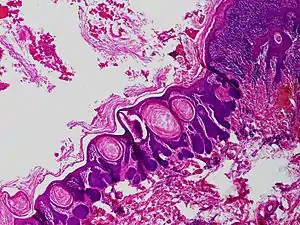

Trichofolliculoma

Trichofolliculoma is a cutaneous condition characterized by a benign, highly structured tumor of the pilosebaceous unit.[1]:671[2]